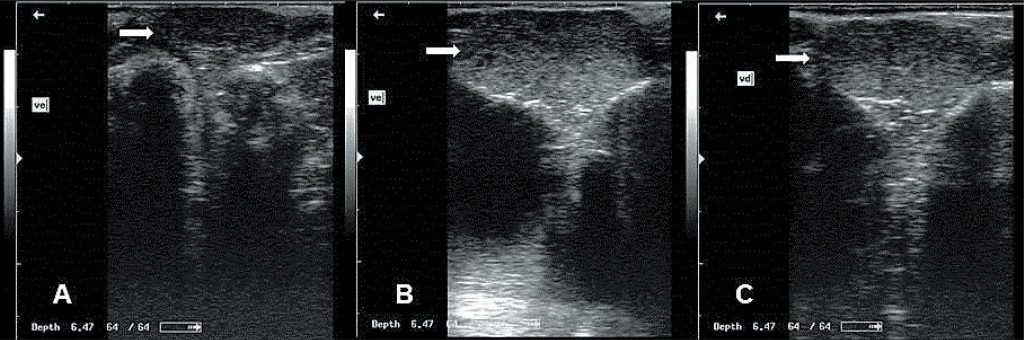

This work aimed to investigate the relationship between echogenicity, testicular biometry, and accessory gland biometry and evaluate the echogenicity pattern of these structures in Santa Ines rams. Fifty-four healthy Santa Ines sheep were classified into three age groups: group 1 – 3 to 5 months (pre-pubertal); group 2 – 7 to 11 months (pubertal); and group 3 – 13 to 28 months (sexually mature). The averages of testicular biometry and bulbourethral gland biometry were different among age groups. The testicular parenchyma was homogeneous with low echogenicity (pre-pubertal group) and medium echogenicity (pubertal and sexually mature groups), suggesting that testicular echogenicity can be a helpful tool to identify the start of puberty. The accessory glands were heterogeneous with low echogenicity in all age groups. Correlations were high between weight, biometry of testis and of bulbourethral gland and echogenicity of the accessory glands, indicating that sexually mature rams with higher body development have larger testicles and larger glands. We recommend the use of testicular biometry as a complementary evaluation of the reproductive efficiency of Santa Ines rams. The average values of echogenicity and the biometry of accessory glands are important parameters to assist the selection of breeding rams.